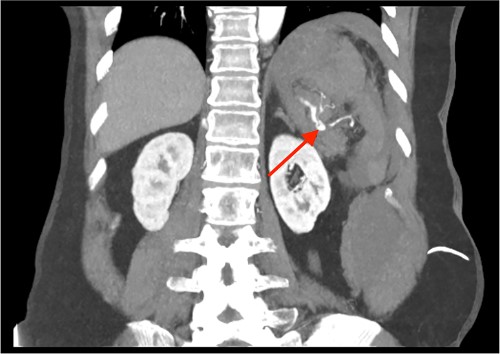

Triple-phase computed tomography (CT) of the abdomen and pelvis revealed a sizeable acute haematoma in the left upper abdomen, below the gastric fundus and body, alongside the pancreatic tail and splenic hilum, extending amongst the proximal small bowel mesentery and into the left subphrenic space. The origin of the haemorrhage appeared to arise from the left upper quadrant. There was a pseudoaneurysm in close proximity to the pancreatic tail and splenic hilum, apparently arising from the adjacent distal splenic artery. CT scan did show local contrast extravasation into the haematoma, as mentioned above (Figs 1–3).

CT of the abdomen and pelvis, coronal plane, arterial phase. Contrast extravasation from the ruptured SAP.